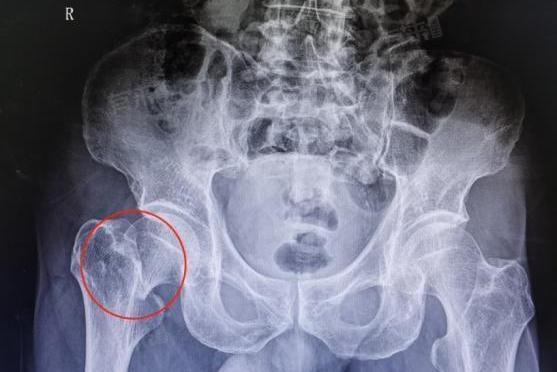

髋关节骨折选择手术治疗还是保守治疗不能一概而论,需要综合多方面因素来考虑。髋关节骨折包括髋臼骨折、股骨颈骨折、股骨粗隆间骨折等不同类型,每种类型在治疗方式的选择上都有其独特的考量。

骨折的类型和严重程度也至关重要。一些移位不明显、稳定性较好的骨折,保守治疗可能就可以达到满意的效果;而对于严重移位、粉碎性的髋关节骨折,手术可能是恢复髋关节正常解剖关系的唯一途径。无论是选择手术还是保守治疗,都需要医生、患者和家属沟通,权衡利弊,选择最适合自己或患者的治疗方案。